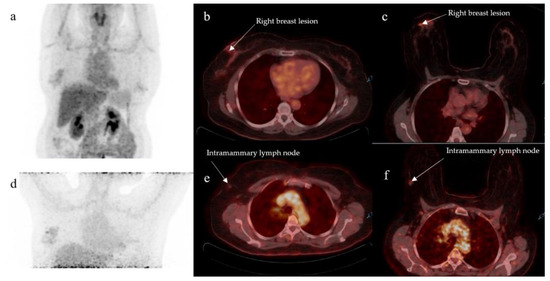

3.2. Lymph Nodes